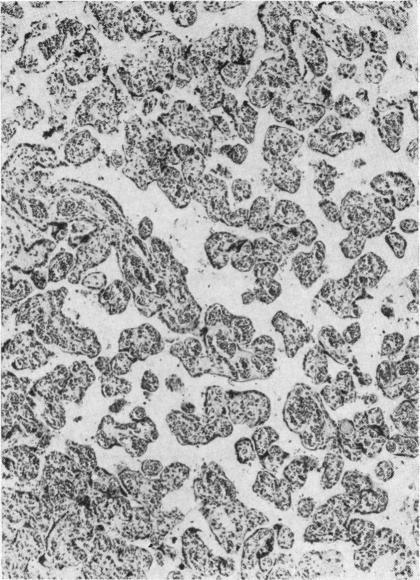

The Placental Transfusion Syndrome in Monozygous Twins.

Arch Dis Child. 1965 Jun;40(211):264-70. doi: 10.1136/adc.40.211.264.